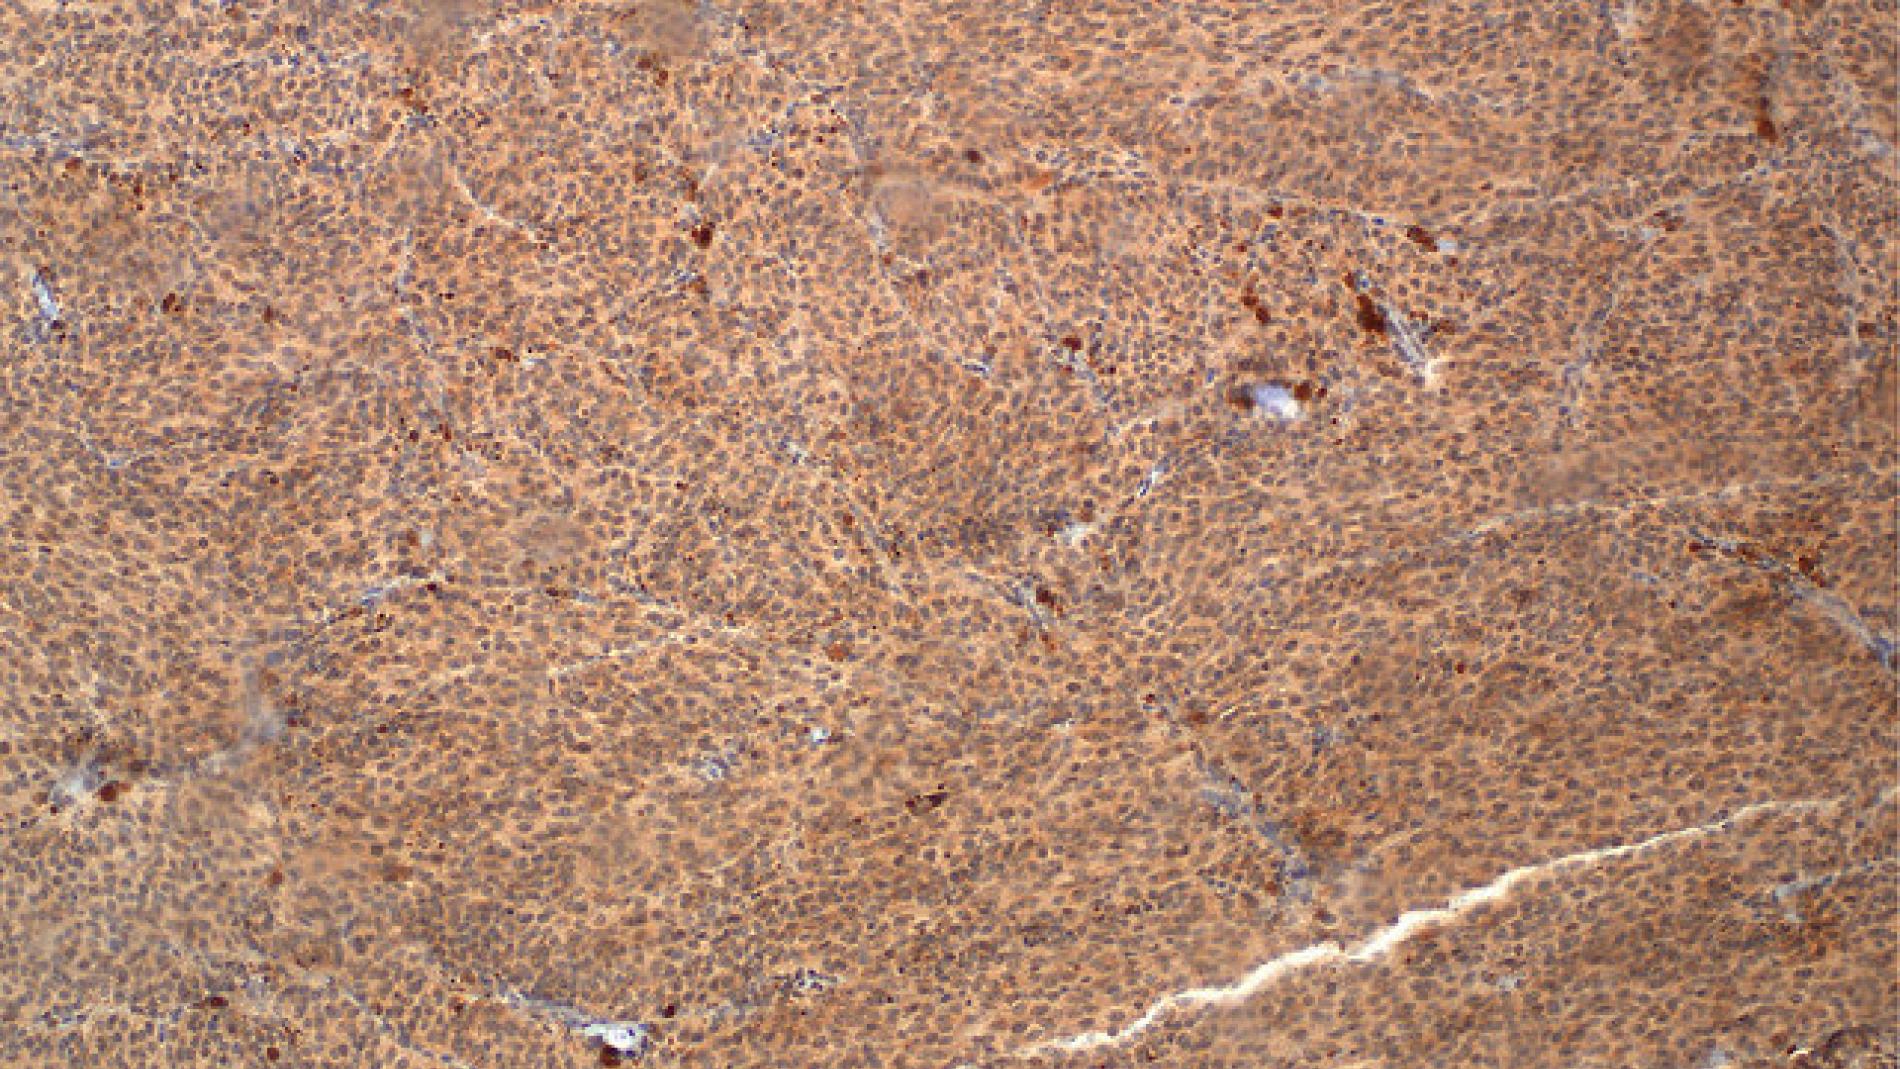

El Dr. Juan ángel Recio, responsable del http://www.vhir.org/portal1/grup-equip2.asp?s=recerca&contentid=186765&t=Recerca%20Biom%E8dica%20en%20Melanoma" grup de Recerca Biomèdica en Melanoma del Vall d'Hebron Institut de Recerca (VHIR) i el Dr. Vicenç García-Patos, cap del Departament de Dermatologia de l'Hospital Vall d'Hebron, han estudiat les alteracions genètiques i l'evolució tumoral en una pacient amb nevus d'Ota que va desenvolupar un melanoma maligne dèrmic, comparant-les amb altres lesions melanocítiques molecularment emparentades. Els resultats de l'estudi, publicats a Pigment Cell and Melanoma Research i Oncotarget, suggereixen la necessitat de recórrer a la combinació de tècniques histològiques i genètiques, per al correcte diagnòstic de molts d'aquests casos. El nevus d'Ota és una malaltia cutània i ocular que consisteix en una hiperpigmentació que afecta a la pell d'un sector de la cara i l'ull, seguint el trajecte del nervi trigemin. Està produït per una proliferació d'unes cèl.lules anomenades melanòcits, que apareixen augmentades en nombre i grandària en aquestes lesions. Tot i que són poc freqüents, s'ha descrit que igual que els melanomes uveals i els nevus blaus, contenen mutacions al gen GNAQ, existint el risc que pugui malignitzar i esdevenir mortal. L'estudi està basat en el cas d'una pacient de 28 anys, que va acudir a l'especialista perquè el quist sebaci que li havien diagnosticat 12 anys enrere havia començat a créixer en els últims 6 mesos. El dermatòleg va decidir extirpar el quist, però el resultat va ser que era un melanoma dèrmic maligne.Al cap d'uns mesos, la pacient va venir recomanada a Vall d'Hebron per fer el seguiment del seu cas, i els oncòlegs Dr. Javier Cortés i Dra. Eva Muñoz-Cosuelo van descobrir que el tumor s'havia desenvolupat al mateix lloc ocupat per un nevus d'Ota localitzat sota el cabell. En aquesta fase va ser quan l'equip del Dr. Recio va analitzar la histopatologia del tumor i les seves característiques moleculars, i va descobrir que el tumor s'havia desenvolupat a partir de la malignització de la lesió benigna (nevus d'Ota) que tenia probablement des del seu naixement. Un any més tard la pacient va desenvolupar un nou tumor exactament a la mateixa zona on es va extirpar el primer. L'anàlisi histològic i genètic de la nova lesió efectuat pel Dr. Recio en col.laboració amb la Dra. Ana Vivancos, responsable del grup de Genòmica de Càncer del Vall d'Hebron Institut d'Oncologia (VHIO), va revelar que el nou tumor era genèticament diferent al primari. Segons l'investigador, "el seguiment de l'evolució de la pacient va permetre evidenciar l'heterogeneïtat tumoral del melanoma a la progressió maligna de la malaltia". Tenir en compte aquesta evolució del tumor és important, ja que les teràpies dirigides contra el càncer es basen en la detecció d'alteracions genètiques en un o diversos gens.Donada l'evolució observada en aquest tipus de càncer dèrmic, el Dr. Recio assegura que el coneixement del tumor i de les mutacions que coexisteixen en una mateixa cèl.lula tumoral "és essencial per entendre els mecanismes convergents implicats en la progressió, establir el pronòstic i administrar teràpies efectives". Després d'aquest cas, els investigadors van analitzar l'evolució de les mutacions implicades en la malignització d'unes lesions emparentades, els nevus blaus, ja que aquests comparteixen amb el nevus d'Ota i els melanomes uveals les mutacions iniciadores de la lesió (GNAQ). Els anàlisis efectuats al melanoma desenvolupat a partir del nevus d'Ota van mostrar que desenvolupaven la mateixa mutació maligna observada als melanomes uveals, que impedia l'activitat de la proteïna BAP1. En canvi, el nevus blau no presentava aquella mutació, malgrat estar també relacionat amb la possibilitat de malignitzar-se i acabar amb un desenllaç fatal. Per determinar què estava succeint, els investigadors van mirar les cèl.lules malignes del nevus blau amb tècniques histològiques i van descobrir que efectivament, la proteïna BAP 1 estava present, però no podia realitzar la seva funció normal per estar deslocalitzada, en lloc d'estar al nucli de la cèl.lula, es localitzava al citoplasma. De manera que aquests tumors havien seleccionat en la seva evolució maligna un mecanisme diferent per arribar al mateix fi, inactivar BAP1. Per això, el Dr. Recio assegura que "la genètica a vegades no és suficient per al diagnòstic ni el pronòstic correcte", ja que en aquest cas el gen buscat no es trobava mutat, però no podia realitzar la seva funció correctament. Gràcies a l'estudi del seu cas, la pacient va poder rebre un tractament personalitzat d'acord amb les particularitats de la seva malaltia. En l'actualitat la pacient està neta de malaltia.